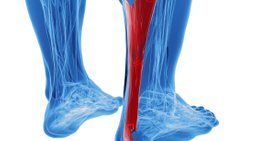

Als Facharzt für Orthopädie und Orthopädische Chirurgie habe ich mich auf die Behandlung von Verletzungen und Erkrankungen des Fußes, des Knies und der Hüfte spezialisiert.

Übermäßige Beanspruchung, Verletzungen sowie angeborene und erworbene Fehlbildungen des Fußes und des Beines können sich negativ auf die Beweglichkeit und Lebensqualität auswirken und zu zahlreichen Folgeerkrankungen und Fehlhaltungen führen. Dank meiner langjährigen Erfahrung bin ich mit unterschiedlichsten Formen von Beeinträchtigungen und Problemen des Vor- und Rückfußes und der unteren Extremität bestens vertraut und kann meinen Patienten eine umfassende Betreuung bieten, die darauf abzielt, dass Sie sich wieder schmerzfrei durch den Alltag bewegen können.

Sehnenpathologien